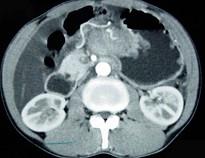

问题 男,65岁,中上腹痛腹胀、消瘦、乏力、纳差,影像检查如图,最可能的诊断是 ( )

选项 A.胃间质瘤 B.萎缩性胃炎 C.肥厚性胃炎 D.胃窦癌 E.胃淋巴瘤

答案 D